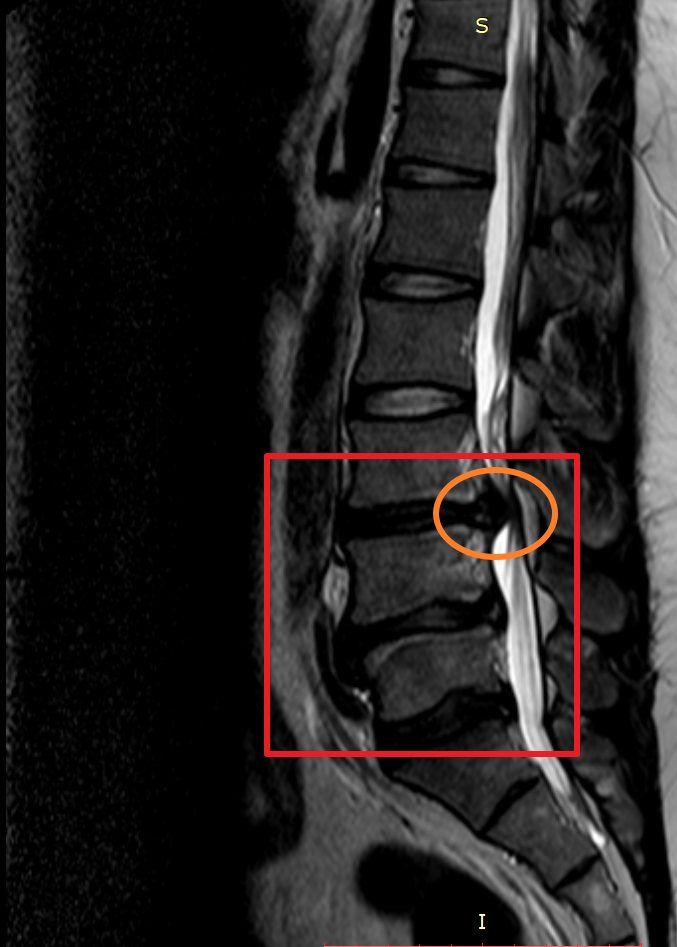

마지막으로 제가 촬영했었던 MRI 촬영 이미지를 첨부해 볼까 합니다. 이미지 순서대로 2014년, 2018년, 2020년 촬영했던 MRI 사진입니다. MRI 촬영 당시 허리디스크 상태가 좋지 않은 상황에서만 세 차례 찍었던 것이기에 이점도 고려해서 참고하시면 좋을 듯합니다.

이미지를 보시면 빨간색 네모 칸에 하얀색 기다란 세로 라인이 신경이 지나가는 부분이며 가장 바깥쪽 두꺼운 흰색 부분은 배 쪽의 지방입니다.

2020년 첫번째, 두번째 터졌던 허리디스크가 많이 흡수되어 신경을 누르고 있는 디스크 압박이 많이 좋아졌으나 세번째 허리디스크가 터진 곳이 심해진 상황.